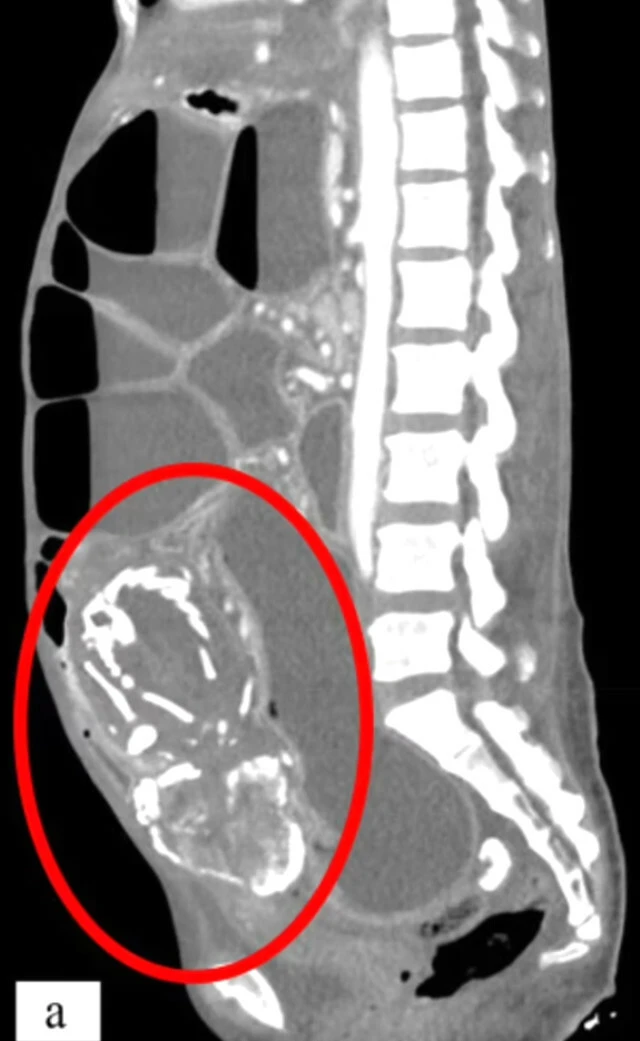

New York'tas hayatını idame ettiren 50 yaşındaki bir kadın, şiddetli karın ağrısı şikayetiyle doktora başvurdu. Doktorlar, incelemelerini tamamladıklarında ise oldukça ilginç bir durum ile karşı karşıya olduklarını fark ettiler. Kadının 9 yıl önce rahmi yerine bağırsaklarında bir cenin meydana geldi ve bu cenin zamanla taşa dönüştü. Taşlaşan cenin, kadının bağırsaklarını tıkadı ve zamanla vücut besinleri emmemeye başladı. Uzun süre besinsiz kalan vücut iflas etti ve kadın hayatını kaybetti.

Şu ana kadar 300 kez meydana gelen vakada, cenin rahimde değil bağırsaklarda bir süre geliştikten sonra ölüyor. Zamanla taşa dönüşen cenin, kişinin sağlığını ciddi şekilde tehlikeye atıp bazı durumlarda ölüme sebep oluyor.